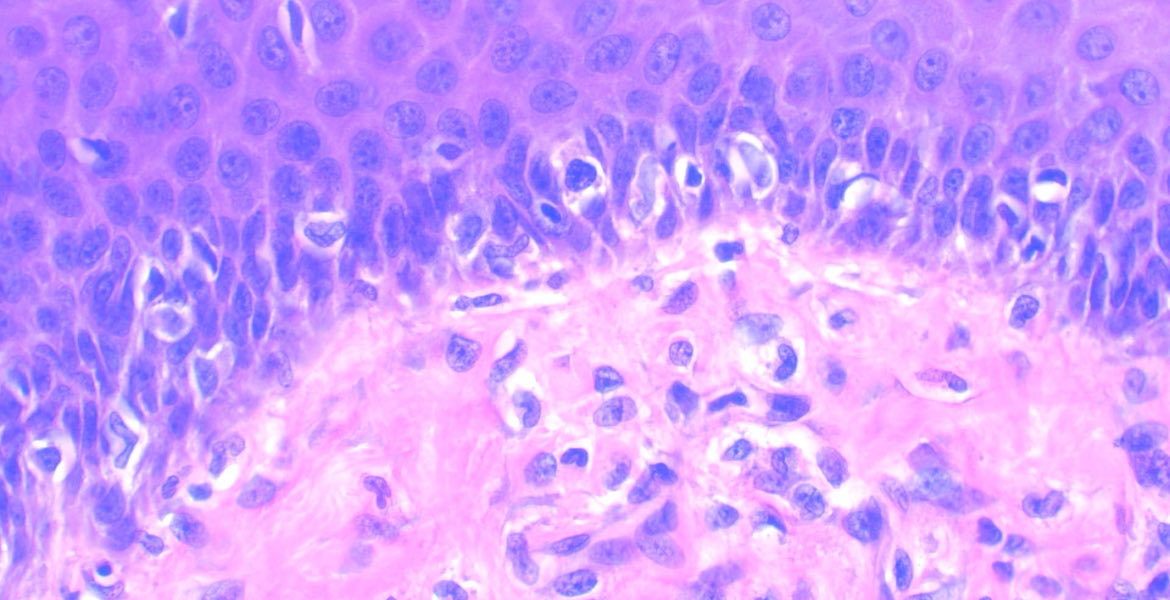

Uterine carcinosarcoma showing serous epithelial carcinoma and liposarcomatous heterologous element 🧐🧐 #Gynecology #WomensHealth #medicine #path #pathology